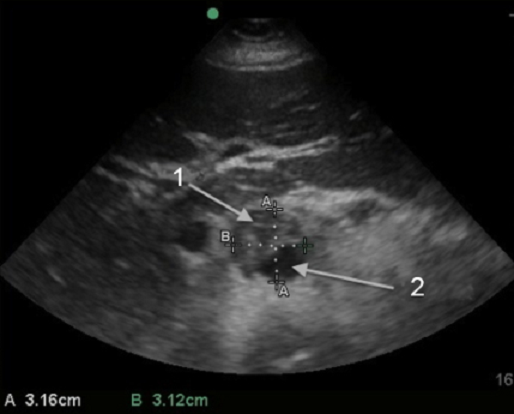

主动脉小腹主动脉瘤 (AAA) 含血栓图像

主动脉 (Ao)

Lumen(内腔)